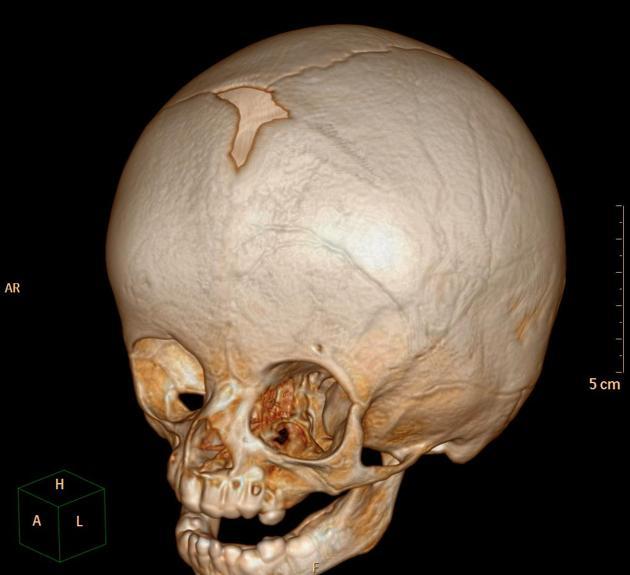

Positional plagyocephaly vs lambdoid cranyosynosthosis

A

Positional: Weeks after birth, ipsiltareal ear moves anteriorly, frontal bossing ipsilateral.

Lambdoid craniosynostosis: Birth, ipsilateral ear moves posterior/inferior and frontal bosing contralateral. extremely rare. see example. SURGERY (allow normal development of brain)